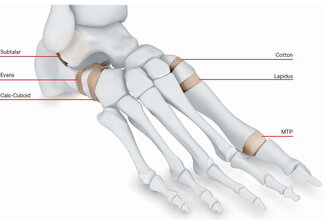

Dense cancellous bio-implants offered in a variety of shapes and sizes for use in foot and ankle procedures.1

Intended to be used for surgical reconstruction for bone fractures, fusions, or osteotomies in the foot and ankle.1